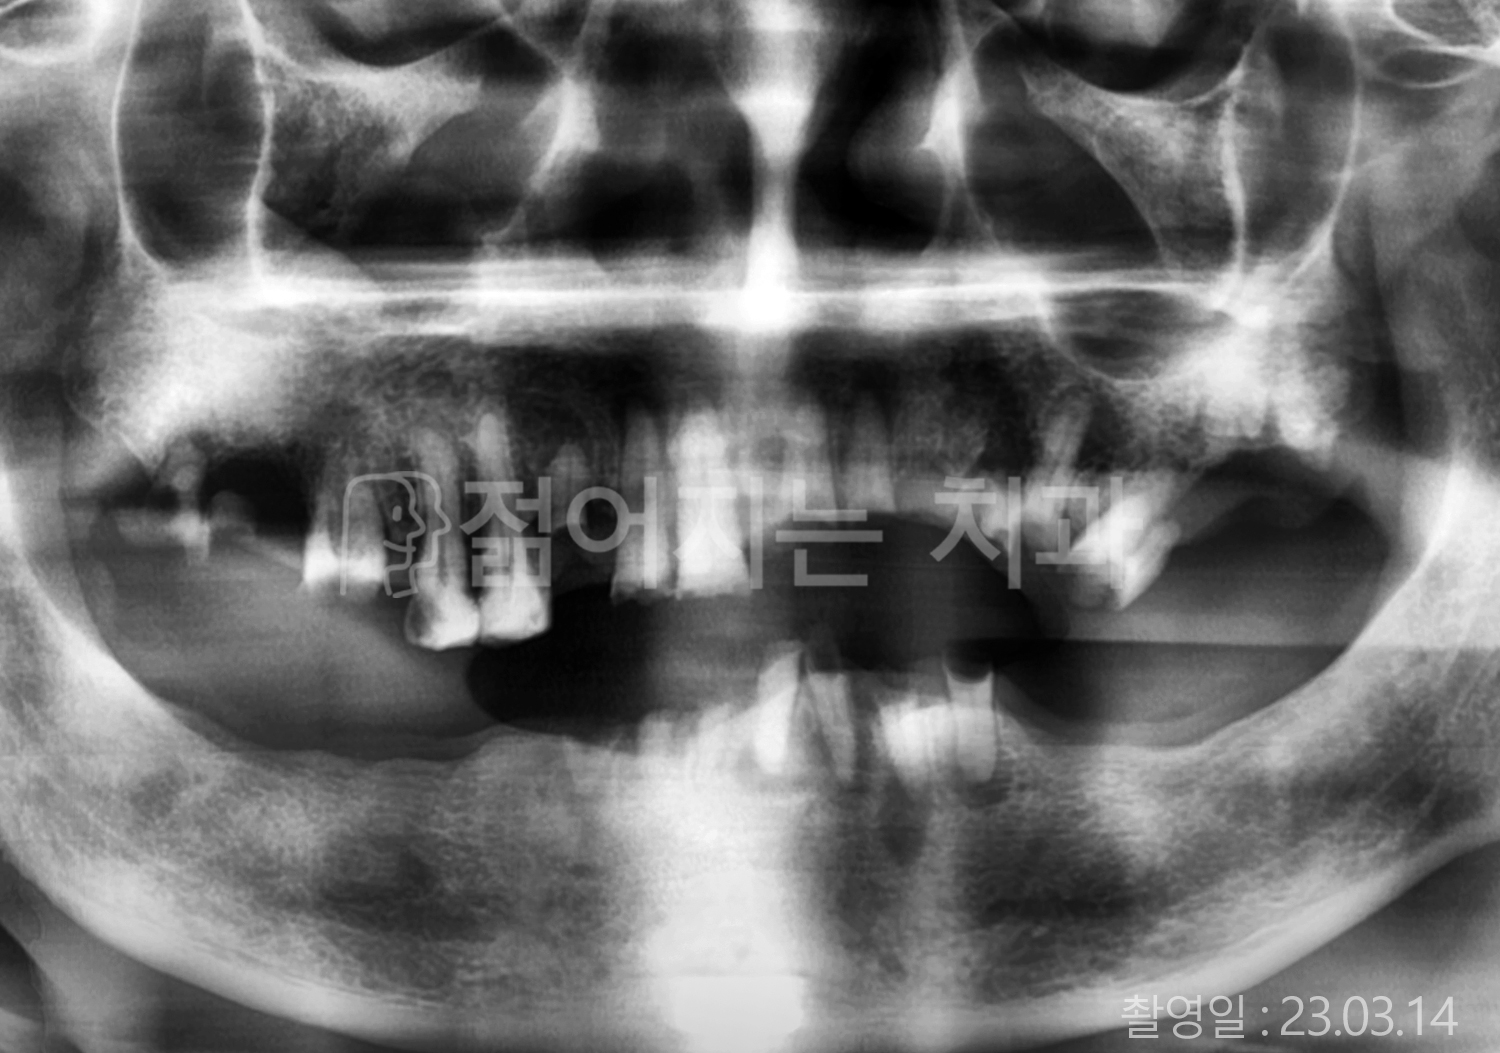

• 60대 전체치아 10개 이상 임플란트